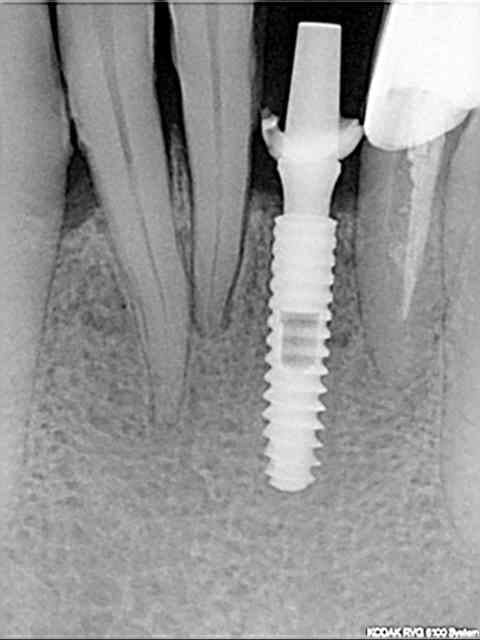

photo 1: début du cas

photo 2: fin d'intervention

photo 3: j+3mois

rx à j=0 et j+4 mois

ce qui est surprenant , c'est la présence d'os au niveau du col.

> rx à j=0 et j+4 mois

>

Oui on connait chez Leone mais reproductible sur toute la gamme. C'est qu"est que je dit! Mais nous c'est démontable et indexé. Un vieux cas en rx 5 ans entre les deux rx.